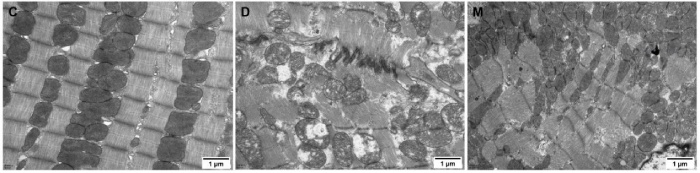

該研究利用透射電鏡測定了MOTS-c對糖尿病心肌超微結(jié)構(gòu)的影響。糖尿病引起心肌纖維排列紊亂和線粒體結(jié)構(gòu)的異常改變,包括心肌細胞排列不規(guī)則、嵴破裂、腫脹和空泡化(圖2)。MOTS-c治療糖尿病大鼠顯著降低心肌線粒體損傷,改善心肌纖維和線粒體結(jié)構(gòu)(圖2)。研究還通過測定檸檬酸合酶的活性,測定了線粒體功能。D組大鼠檸檬酸合酶的活性顯著降低,C組和M組的檸檬酸合酶的活性無統(tǒng)計學(xué)差異(圖3g)。

圖2. 各組大鼠心肌組織透射電鏡圖像